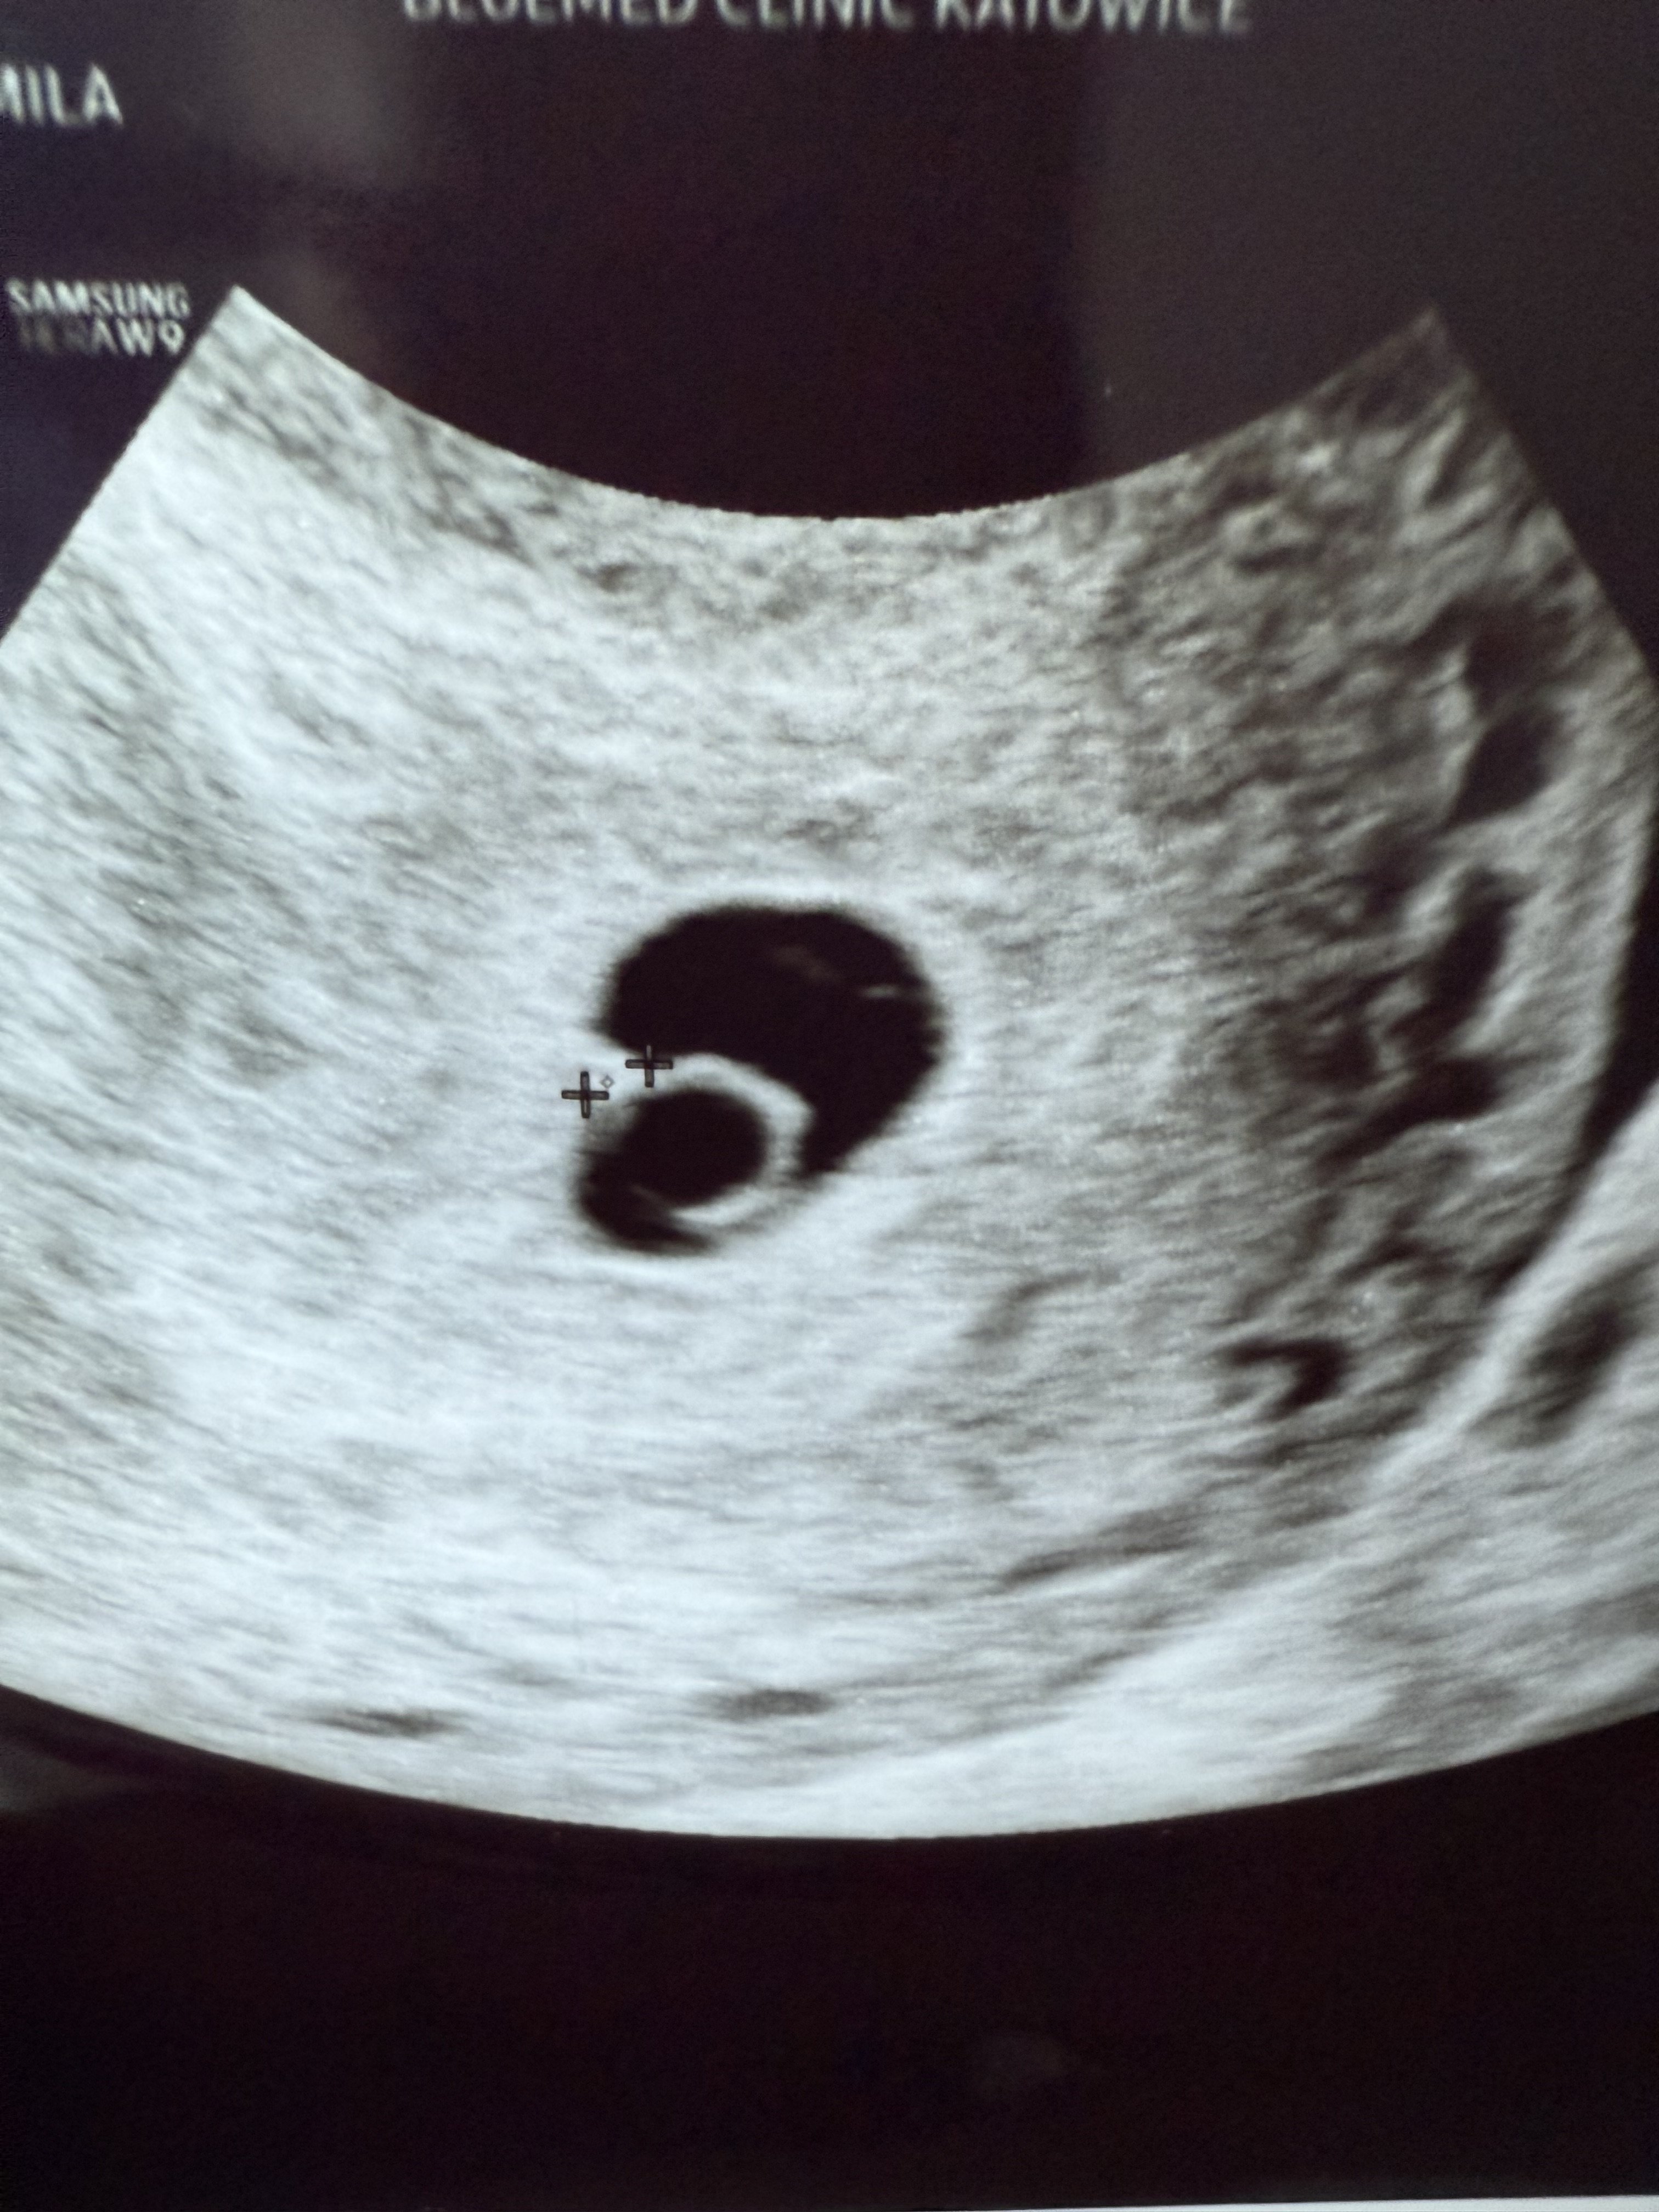

Meldujemy się w czwartek z 1,5mm Kajtkiem.

Wczorajsza wizyta okej, Kajtek za mały żeby było widać serduszko, ale mam nadzieję, że na kolejnej wizycie 27.06 (7+1) już zmierzymy fhr i wszystko będzie okej. Wczoraj 5+6, więc dobrze, że w ogóle Pani Doktor Kajtka znalazła, a nie tylko same pęcherzyki.